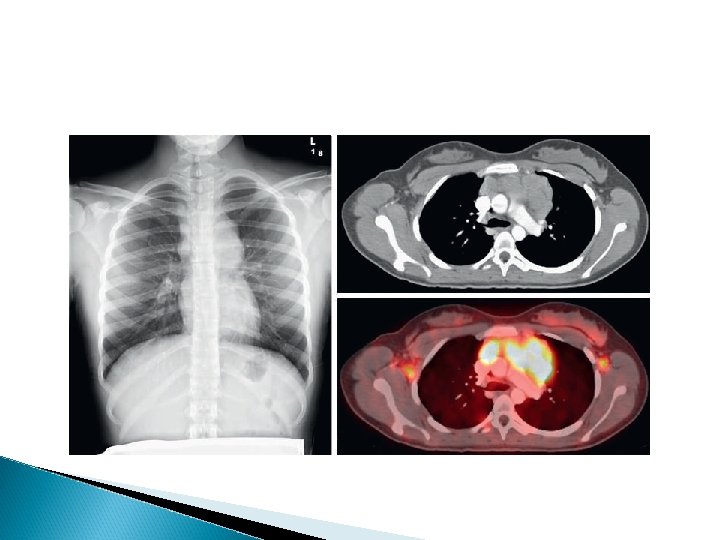

DIAGNOSIS Any patient with persistent, unexplained lymphadenopathy unassociated with an obvious underlying inflammatory or infectious process should undergo chest radiography to identify the presence of a large mediastinal mass before undergoing lymph node biopsy. Formal excisional biopsy is preferred over needle biopsy to ensure that adequate tissue is obtained, both for light microscopy and for appropriate immunohistochemical and molecular studies

Once the diagnosis of HL is established, extent of disease (stage) should be determined to allow selection of appropriate therapy (Table 496 -2). Evaluation includes history, physical examination, and imaging studies, including chest radiograph; CT scans of the neck, chest, abdomen, and pelvis; and positron emission tomography (PET) scan

A cxr is particularly important for measuring the size of the mediastinal mass in relation to the maximal diameter of the thorax This determines “bulk”disease and becomes prognostically significant. Chest CT more clearly defines the extent of a mediastinal mass if present and identifies hilar nodes and pulmonary parenchymal involvement, which may not be evident on chest radiographs.

Fluorodeoxyglucose PET imaging has advantages over gallium scanning, as it is a 1 -day procedure with higher resolution, better dosimetry, less intestinal activity, and the potential to quantify disease. PET scans are being evaluated as a prognostic tool in HL, enabling therapy to be reduced in those predicted to have a good outcome.